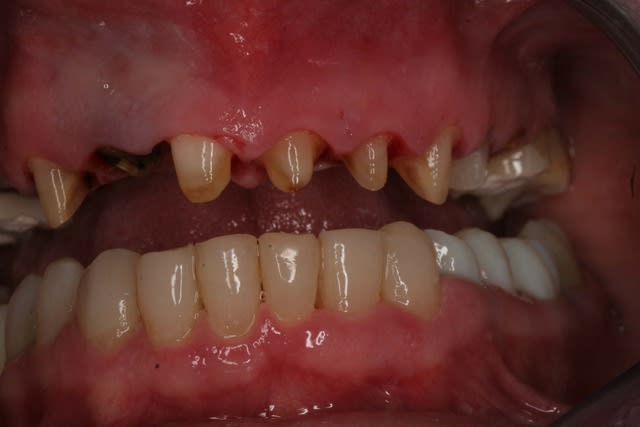

Donc la suite, évidement ortho: ingression du bloc incisivo canin sup avec ré alignement des arcades, extraction de la 14 nécessaire et ré alignement des milieux interincisif.

Pendant la finalisation du haut (axe mésio-disto incisif, à corriger à la fin pour faciliter gingivoplastie incisif sup). Il y a eu composite vestibulaire pelliculaire sous digue de 33 à 43, reprise soins et ancrage + provisoires 34,35, 36, 46; et composite sous digue 37 et 47.

Voila la suite pour le maxillaire, le wax est fait sur arti en fonction de l'OIM obtenue après ortho. seule la 27 restera intacte.

Préparation des molaires pour permettre des RTE sous digue à travers les provisoires, retrait des anciennes couronnes et ancrages sur les 12, 15 et 25 endo satisfaisantes (couronnes ayant plus de 30 ans pour certaines!!!.

Tailles parallèles pour zircone 13 à 23 seront solidarisées pour éviter une migration post ortho.

Gingivectomie légère à la fraise à biseau pour harmoniser les collets, mais l'ortho a permis d'énormément faciliter ce travail.